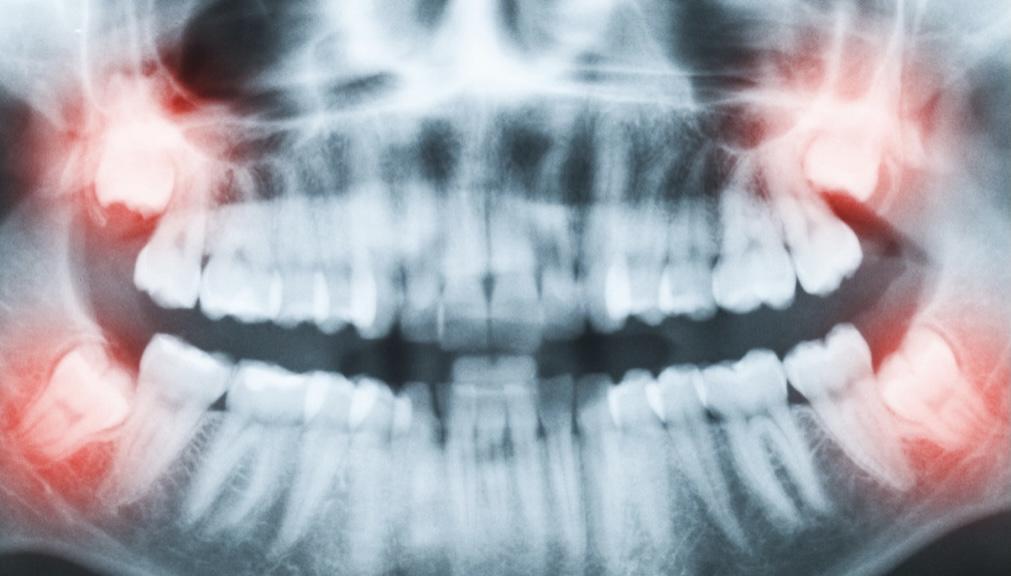

當然,還有其他更加奇奇怪怪的pose……

各類“不聽話的”下頜智齒